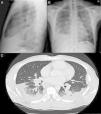

(A) PA chest radiograph. (B) Radiograph of lateral thorax, showing patchy alveolar infiltrates in the left middle and upper lobes. Predominantly right-sided bilateral pleural effusion. Hilar and mediastinal lymphadenopathy of pathological appearance. (C) Axial image of chest CT with intravenous contrast medium showing lymphadenopathy component in the mediastinal, bilateral hilar and periesophageal compartments. Bilateral alveolar involvement predominantly in the subpleural region of both bases, with accumulated nodal lesions and patchy air bronchogram in the subpleural region.

A 38-year-old man, native of Ghana, diagnosed in 2003 with latent tuberculosis (TB), no chemoprophylaxis administered. Episodes of malaria during infancy. He consulted due to a 2-month history of cough, with bloody expectoration, dyspnea, pleuritic chest pain, with weight loss, Afebrile. Of note on physical examination were hypophonesis in the right lung base with crackles and rhonchi up to the middle fields in both sides. Chest radiography revealed bilateral multiple basal alveolar infiltrates with hila of nodular appearance, suggestive of lymphadenopathies, along with right PE (Fig. 1A and B). Of note on clinical laboratory tests: LDH 134, with reduced proteins and albumin, CRP 63mg/dl and ESR 47. Protein electrophoresis spectrum with inflammatory pattern with no monoclonal peak, negative autoimmunity and negative HIV and HCV serologies, previous HBV and HAV. ACE 89.2 (normal<50). Negative for Mantoux booster phenomenon. Serous fluid obtained on thoracocentesis consistent with predominantly lymphocytic exudate, ADA 72. Mycobacteria and fungus-specific staining, cultures and molecular techniques were negative; immunophenotyping showed no clonality but did reveal a significant T cell population with a CD4+/CD8+ ratio of 4/1 (>3.5). After a chest-abdominal PET-CT (Fig. 1C), a bronchoscopy was performed and a transbronchial biopsy obtained, showing necrotizing non-caseifying epithelioid granulomas. Final diagnosis of pulmonary sarcoidosis stage II with secondary PE.